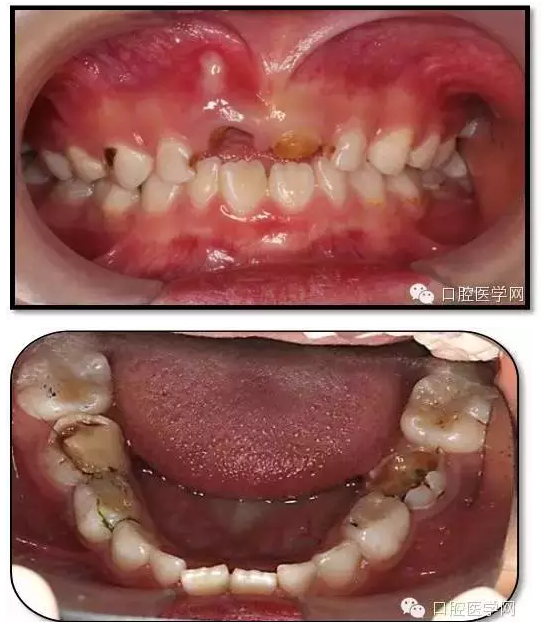

患兒,女,6歲1個月

主訴:坐下后牙頰側(cè)牙床鼓膿包2周

現(xiàn)病史:左下后牙頰側(cè)牙床鼓膿包2周,左側(cè)進食疼痛,來診求治?;純簭?歲開始刷牙,父母幾乎不幫助刷牙。從沒用過牙線,愛吃甜食,偶爾睡前吃甜食。雙側(cè)下后牙1年前在我院兒科行根管治療。

既往史:84、85、75在1年前我院兒童口腔科行根管治療史。

查體、輔查

臨床檢查: 75OL齲洞, 舌側(cè)牙體完全劈裂斷端齊齦,探及大量軟化腐質(zhì)。頰側(cè)牙齦紅腫見瘺管,擠壓大量溢膿。叩(±),不松動。X線:75根管空虛,牙根吸收約1/2,根尖周及根分歧大面積透射影,35發(fā)育4期,骨硬板尚連續(xù);51殘根,唇側(cè)牙齦瘺管,叩(±),不松動。X線:51牙根吸收約1/2,根尖周低密度影。

85O、84DO充填體邊緣不密合,叩(±),不松動。84頰側(cè)牙齦略紅腫。X線:84遠中根及髓室底完全吸收,根分歧透射影,近中根內(nèi)側(cè)見外吸收,44上方骨硬板連續(xù)。85近中根完全吸收,髓室底吸收,根分岐透射影,遠中根管內(nèi)見根充影像。45發(fā)育4期,骨硬板連續(xù)。

55OL、65OL、74O、53DL齲洞,叩(-),不松動,齦無異常。

16OL、46OB、26O、36OB窩溝探及淺齲壞,叩(-),不松動,齦無異常。